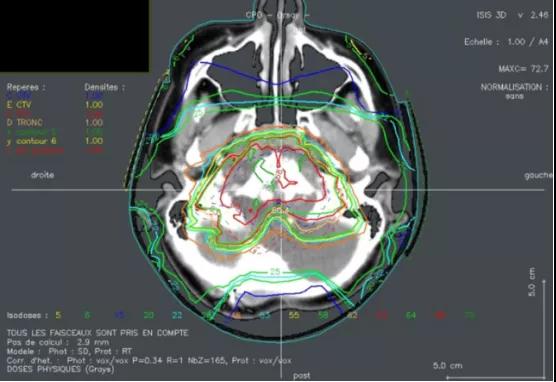

脊索瘤是一種十分罕見(jiàn)的原發(fā)性惡性骨腫瘤,手術(shù)難以完全切除,傳統(tǒng)的放療可能導(dǎo)致脊索瘤患者出現(xiàn)嚴(yán)重的放療副反應(yīng),如視力喪失、聽(tīng)力喪失、腦干損傷等等,嚴(yán)重降低患者后續(xù)的生活質(zhì)量。因此對(duì)于脊索瘤患者而言,需要更有效的、副作用更低的治療手段。質(zhì)子治療作為新興的放療技術(shù),具有精度高、能量集中,副作用小等優(yōu)勢(shì),在治療脊索瘤領(lǐng)域也有著突出的效果。

▲質(zhì)子治療脊索瘤的劑量分布圖,圖源:參考文獻(xiàn)[4]

[4] Chordoma in children: Case-report and review of literature

https://www.sciencedirect.com/science/article/pii/S1507136715001406